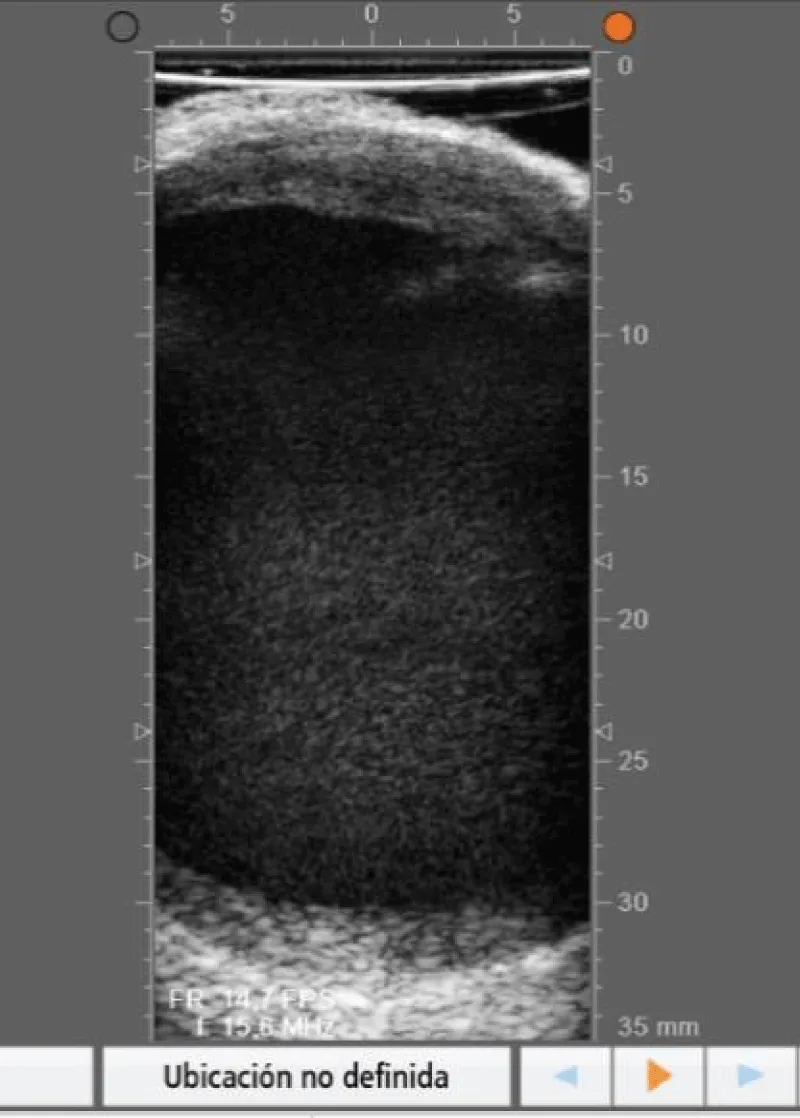

- In redo’s when the first CABG was performed, it allows to precisely locate the course of the previous grafts (Figure 19).

Figure 19: Location with epicardic echography of the course of an internal mammary artery anastomosed to the left anterior descending artery, in a patient reoperated, in whose first intervention a cardiac surgical revascularization was performed.

- In redo’s when myocardial revascularization has to be performed in the present surgery, or in patients with an important amount of pericardial fat, it allows to precisely locate the course of the coronary arteries.